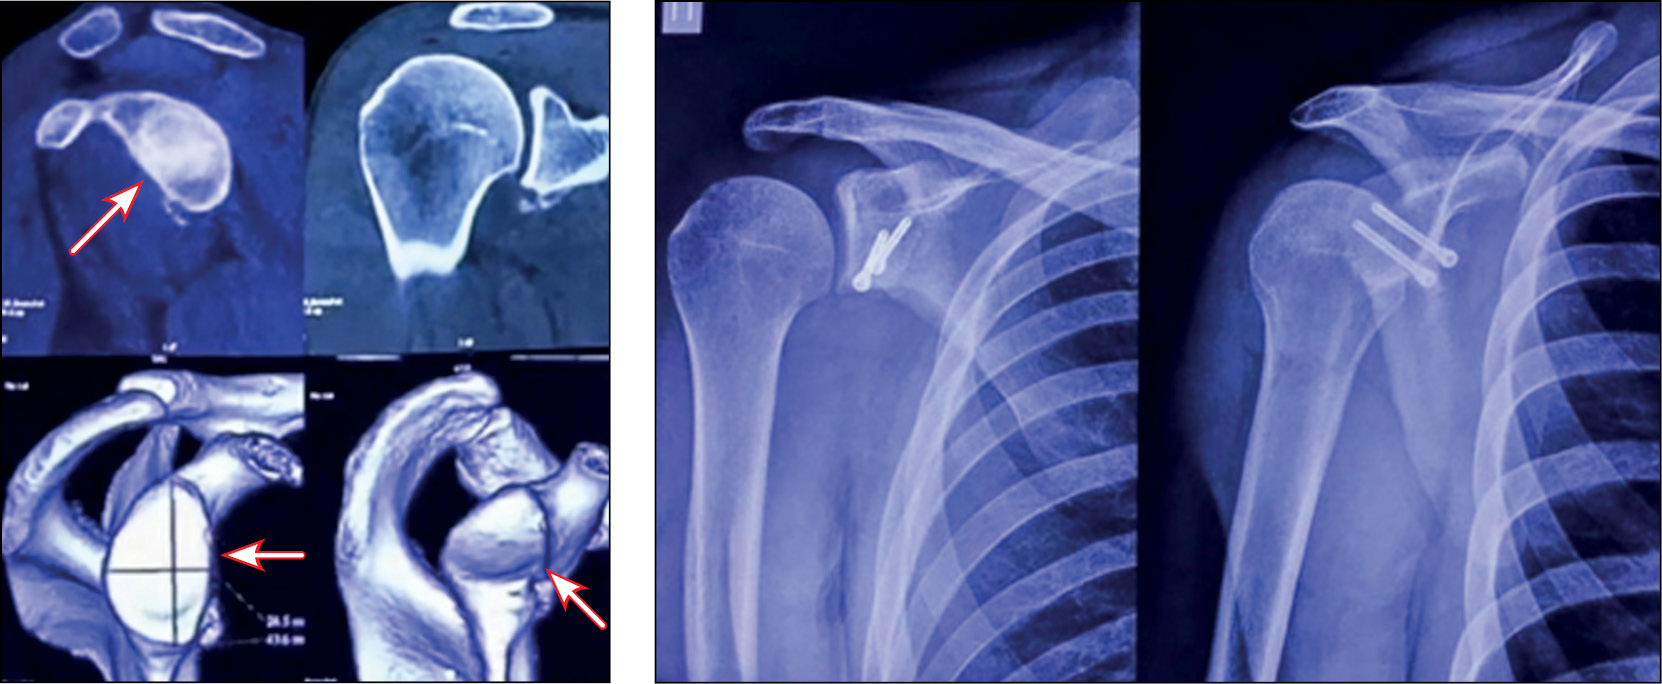

Пациент Д., 30 лет, с диагнозом «рецидивирующая нестабильность левого плечевого сустава» (мастер спорта международного класса по самбо). В 2022 году выполнена артроскопическая операция Латарже левого плечевого сустава.

Проведена компьютерная томография до операции и рентгенография через 6 мес после вмешательства. Исследование спустя 7 месяцев после хирургического лечения. Клиническая оценка результата хорошая, рецидивов нет, имеется небольшое ограничение наружной ротации плеча (рис. 10).

Рис. 10. Костный дефект гленоида на предоперационной компьютерной томографии, контрольная рентгенография через 6 месяцев после операции.

Fig. 10. Bone defect of the glenoid on preoperative computed tomography, control radiography 6 months after surgery.